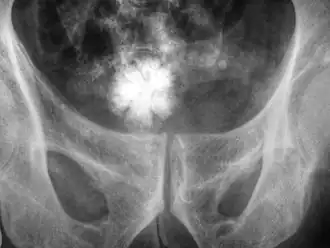

Op deze röntgenfoto is een stervormige blaassteen zichtbaar.